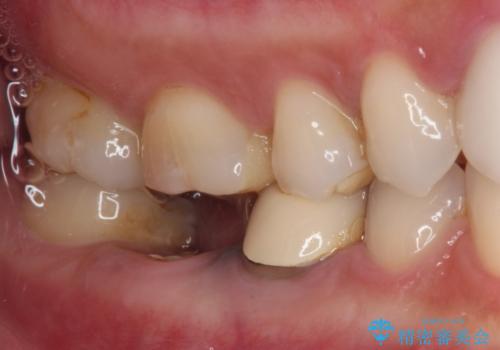

- 他院で治療を開始したものの抜歯が必要と言われ、何とか残せないものかとのことで来院された患者様です。

下顎大臼歯は歯冠部分が残っておらず、保存が難しいように思えましたが、まずは根管治療を行った上で補綴治療を行うこととしました。

上顎臼歯は、おそらく銀歯を外して仮詰めされていたため、再度形を整え、セラミックインレーにて修復治療を行うこととしました。